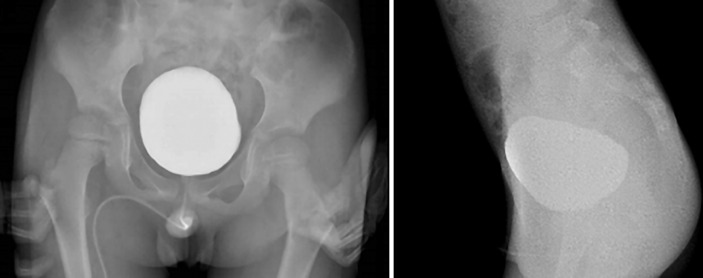

Case presentation: We present a case of intermittent urinary retention resulting from a stone obstructing the PUV. The patient experienced intermittent urinary retention for over a month. A computed tomography scan revealed a bladder stone in the posterior urethra. The intracorporeal lithotripsy for calculus with fulguration of the PUV was performed using holmium:YAG laser.